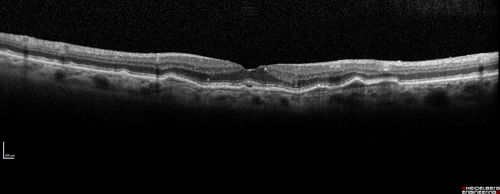

Asymptomatic wet AMD - Subfoveal CNM both eyes

82 year old woman - 20/25 OU. Images show occult subfoveal CNVM both eyes best seen on late ICG.  The left eye also has probable polypoidal choroidal vasculopathy.  No treatment was recommended on the first visit - follow-up at 1 month.